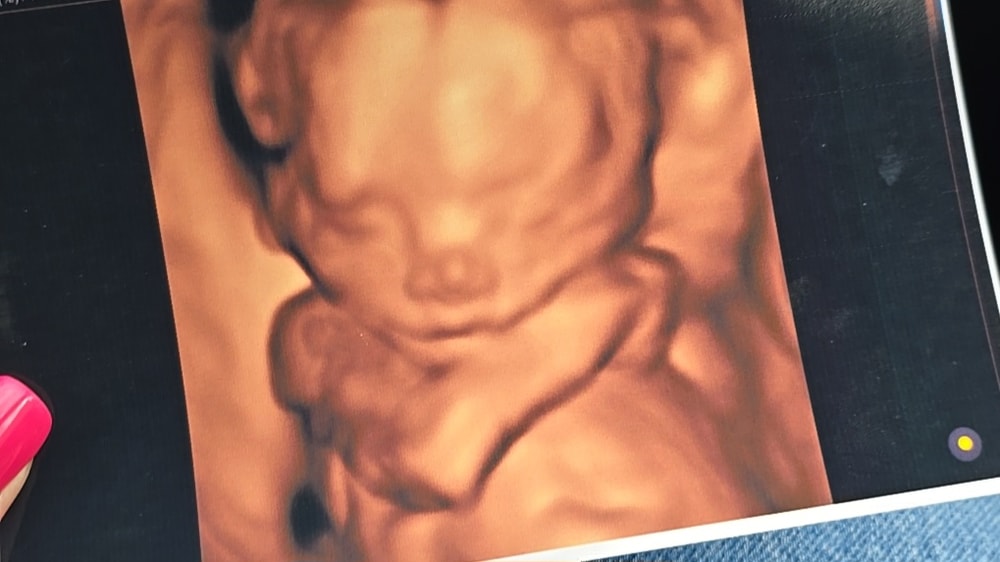

19 недель беременности 🩷3D узи

Даже сделали 3D УЗИ, может, рано еще, но пусть фотки будут. Сразу видно, нос папин. 😊 Лежит, машет ногами и руками, очень активная.